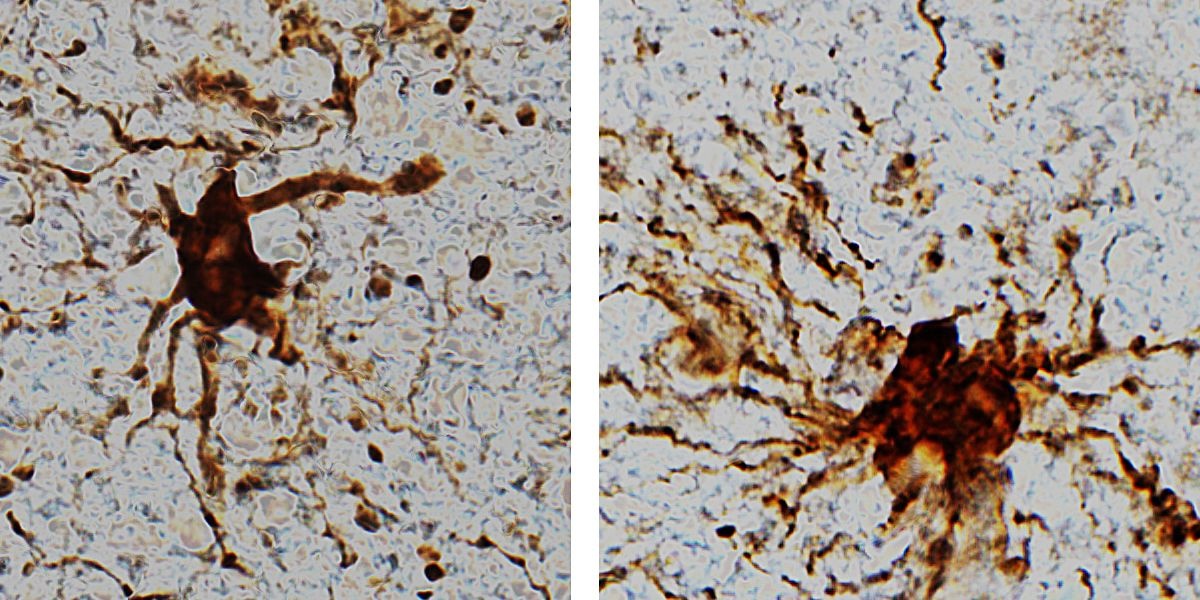

Các nhà nghiên cứu đã phân tích biểu hiện gen từ các mô não sống và phát hiện ra trong một số tế bào, biểu hiện gen đã tăng lên sau khi chết. Họ quan sát thấy các tế bào thần kinh đệm bị viêm phát triển và mọc ra những nhánh dài như cánh tay trong nhiều giờ đồng hồ sau khi chết.

Các gen "zombie" được kích hoạt sau khi não ngừng hoạt động. Chúng là các gen thần kinh đệm chịu trách nhiệm quan tâm đến mô não tổn thương. Ảnh: Tiến sĩ Jeffrey Loeb/UIC.

"Không có gì quá ngạc nhiên khi các tế bào thần kinh đệm phát triển ngay sau khi tim ngừng đập. Những tế bào này bị viêm và nhiệm vụ của chúng là dọn dẹp mọi thứ sau khi não bị tổn thương như thiếu oxy hoặc đột quỵ", Loeb phát biểu trong một thông cáo báo chí của trường đại học. Cũng theo ông, những mối liên quan đều rất đáng chú ý.